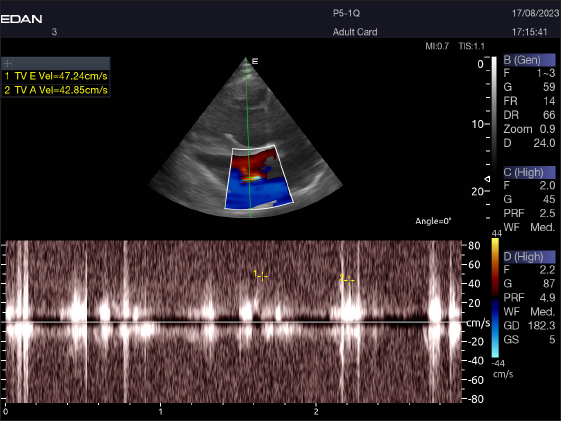

The Mv E/A (Fig. 8), Tv E/A (Fig. 9), and maximum velocity of the aortic valve (Av Vmax) (Fig. 10) were all measured using pulsed-wave Doppler at LPSLAx in all camels. Two cases were observed with mild mitral regurgitation detected through continuous-wave Doppler, but the regurgitation was not considered significant (Fig. 11).

Fig. 9. Left parasternal longitudinal axis of an 18-year-old racing camel showing pulsed wave Doppler over the tricuspid valve (1=E wave and 2=A wave).

Table 4 provides an overview of pulsed-wave Doppler echocardiographic serial measures in adult racing camels. The pulsed-wave Doppler echocardiographic measurements’ mean values ± standard deviation were recorded for Tv E/A (1.3 ± 0.2 cm2), Mv E/A (1.3 ± 0.2 cm2), Av max (−88.2 ± 25.1 cm/second), and Pv max (−59.2467 ± 17.4 cm/second), as shown in Table 4.

The pulsed-wave Doppler echocardiography of racing camels is not well documented. While all camels had their Mv E/A, Tv E/A, and maximum velocity of the Av Vmax recorded using pulsed-wave Doppler at (LPSLAx), the majority of cases (58.4%) had trouble measuring the pulmonary valve from the right short parasternal view. Using continuous-wave Doppler, minor mitral regurgitation was observed in two patients, but the regurgitation was not substantial.